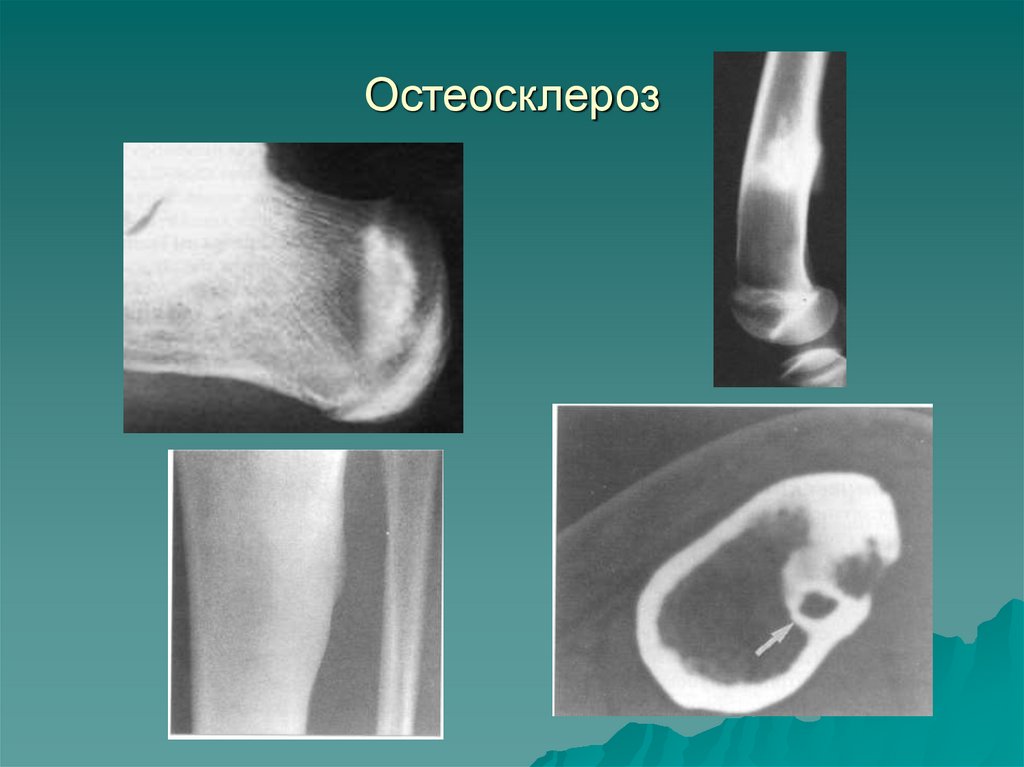

II.2. ОСТЕОСКЛЕРОЗ – увеличение количества

костных балок в единице объема кости

Виды ОС: физиологический (функциональный) в зонах

роста кости, повышенной нагрузки, на суставных

впадинах

Посттравматический (репаративный)

Воспалительный (хронический остеомиелит, сифилис и

др.)

Реактивный (дистрофические, опухолевые процессы)

Токсический (хронические отравления мышьяком,

фосфором)

Идиопатический (аномалии дифференцировки скелета –

мраморная болезнь, остеопойкилия, мелореостоз)

26. Остеосклероз

Рентгенологические

признаки ОС:

- мелкопетлистая

структура губчатого

вещества

- утолщение

кортикального слоя

- сужение просвета

костномозгового

пространства с

возможным полным

закрытием его

(эбурнеация)

- повышение плотности

костной ткани

28.